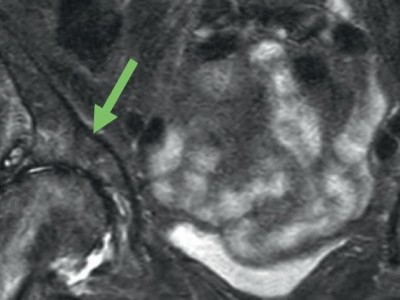

Knieschmerzen diagnostizieren per Ultraschall

Ist das Kniegelenk entzündet? Liegt ein Muskelriss vor? Sind Bänder, Knorpel oder Knochen verletzt? Die Ultraschalluntersuchung kann bei Schmerzen im Knie schnell und zuverlässig die Ursache klären und therapieentscheidend sein.

Untersuchung des Beins eines Patienten/© Visionär / Fotolia, Sonographiequerschnitt über der Hälfte des M. quadriceps (Normalbefund)/© Gehlen M et al. / all rights reserved Springer Medizin Verlag GmbH, Eine Frau hält sich den Fuß am Knöchel/© dragana991 / Getty Images / iStock (Symbolbild mit Fotomodell), ZFA TALKS - Nackenschmerzen/© (M) contrastwerkstatt / Stock.adobe.com (Symbolbild mit Fotomodell), Fortgeschrittene Gonarthrose bei 83-Jähriger/© J. Stöve, Arzt untersucht Senior am Rücken/© miodrag ignjatovic / Getty Images / iStock (Symbolbild mit Fotomodellen), Frau mit Hut im Wald/© (M) encierro / stock.adobe.com (Symbolbild mit Fotomodell), Frau bei Knochenmineraldichte-Messung/© gelmold / stock.adobe.com (Symbolbild mit Fotomodell), Arzt untersucht Patienten mit Rückenschmerzen /© ChesiireCat / Getty Images / iStock (Symbolbild mit Fotomodellen), Frau geht Spazieren/© HODEI / stock.adobe.com (Symbolbild mit Fotomodell), Messung des Kopf-Wand-Abstands/© A. Schuh, Schmerzhafte Schwellung des linken Ellenbogens/© C. Raschka, Hallux rigidus Röntgenbefund/© A. Schuh, Coxarthrose rechts nach Kellgren-Lawrence-Grad III/© Dres. Lieser und Kollegen, Radiologische Praxis Trier, Sonografie am Fußgelenk/© A. Schuh, Gelenkultraschall am Knie/© A. Schuh, MRT bei medialseitiger Gonarthrose mit Knorpelschaden/© Klinikum rechts der Isar, Ultraschall am Ellenbogen/© A. Schuh, Position des Schallkopfs ventral an der Schulter/© So wie es am Bild steht, Röntgenaufnahmen von Valgus- und Varusachsen/© Schubert I et al. / all rights reserved Springer Medizin Verlag GmbH, Achillessehnenruptur/© Z. Binder, Ärztin behandelt Fußballspielerin mit Kopfverletzung/© rocketclips / stock.adobe.com (Symbolbild mit Fotomodell), Patientin mit Gonarthrose/© (M) FluxFactory / Getty Images / iStock (Symbolbild mit Fotomodellen), Search Icon, Die Leitlinien für Ärztinnen und Ärzte, Facharzttraining Allgemeinmedizin, Hand hält Laborröhrchen/© Kunstzeug / stock.adobe.com (Symbolbild mit Fotomodell), Läufer umfasst sein Sprunggelenk/© PeopleImages / Getty Images / iStock (Symbolbild mit Fotomodell), Herpes Zoster am Rücken/© Mumemories / Getty Images / iStock (Symbolbild mit Fotomodell), EKG befunden mit System - EKG Essential/© Springer Medizin Verlag GmbH